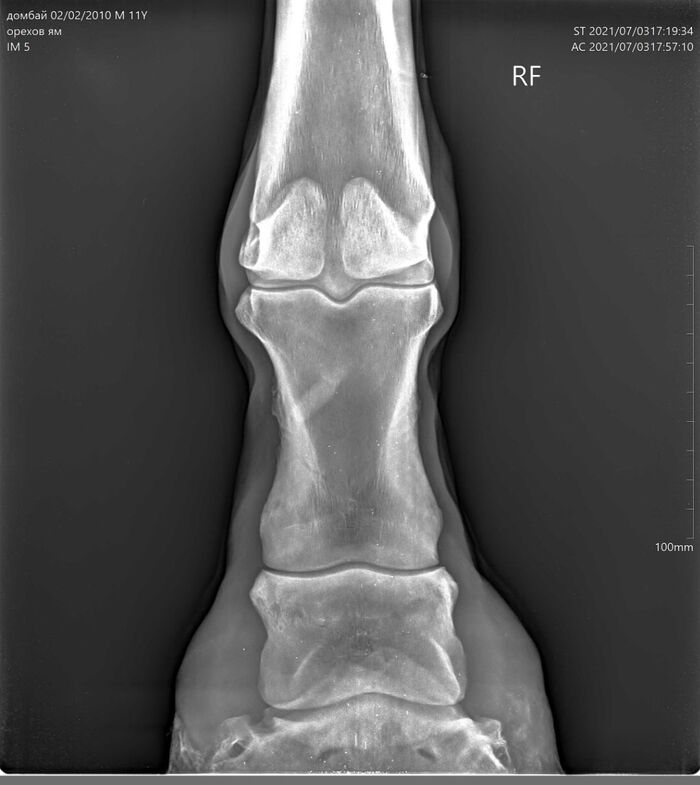

На этих x-ray снимках Домбай.

У него артроз (или артрит, я такой себе врач) пальчиков на руках.

Плюс косточка в копыте подходит очень близко к краю.